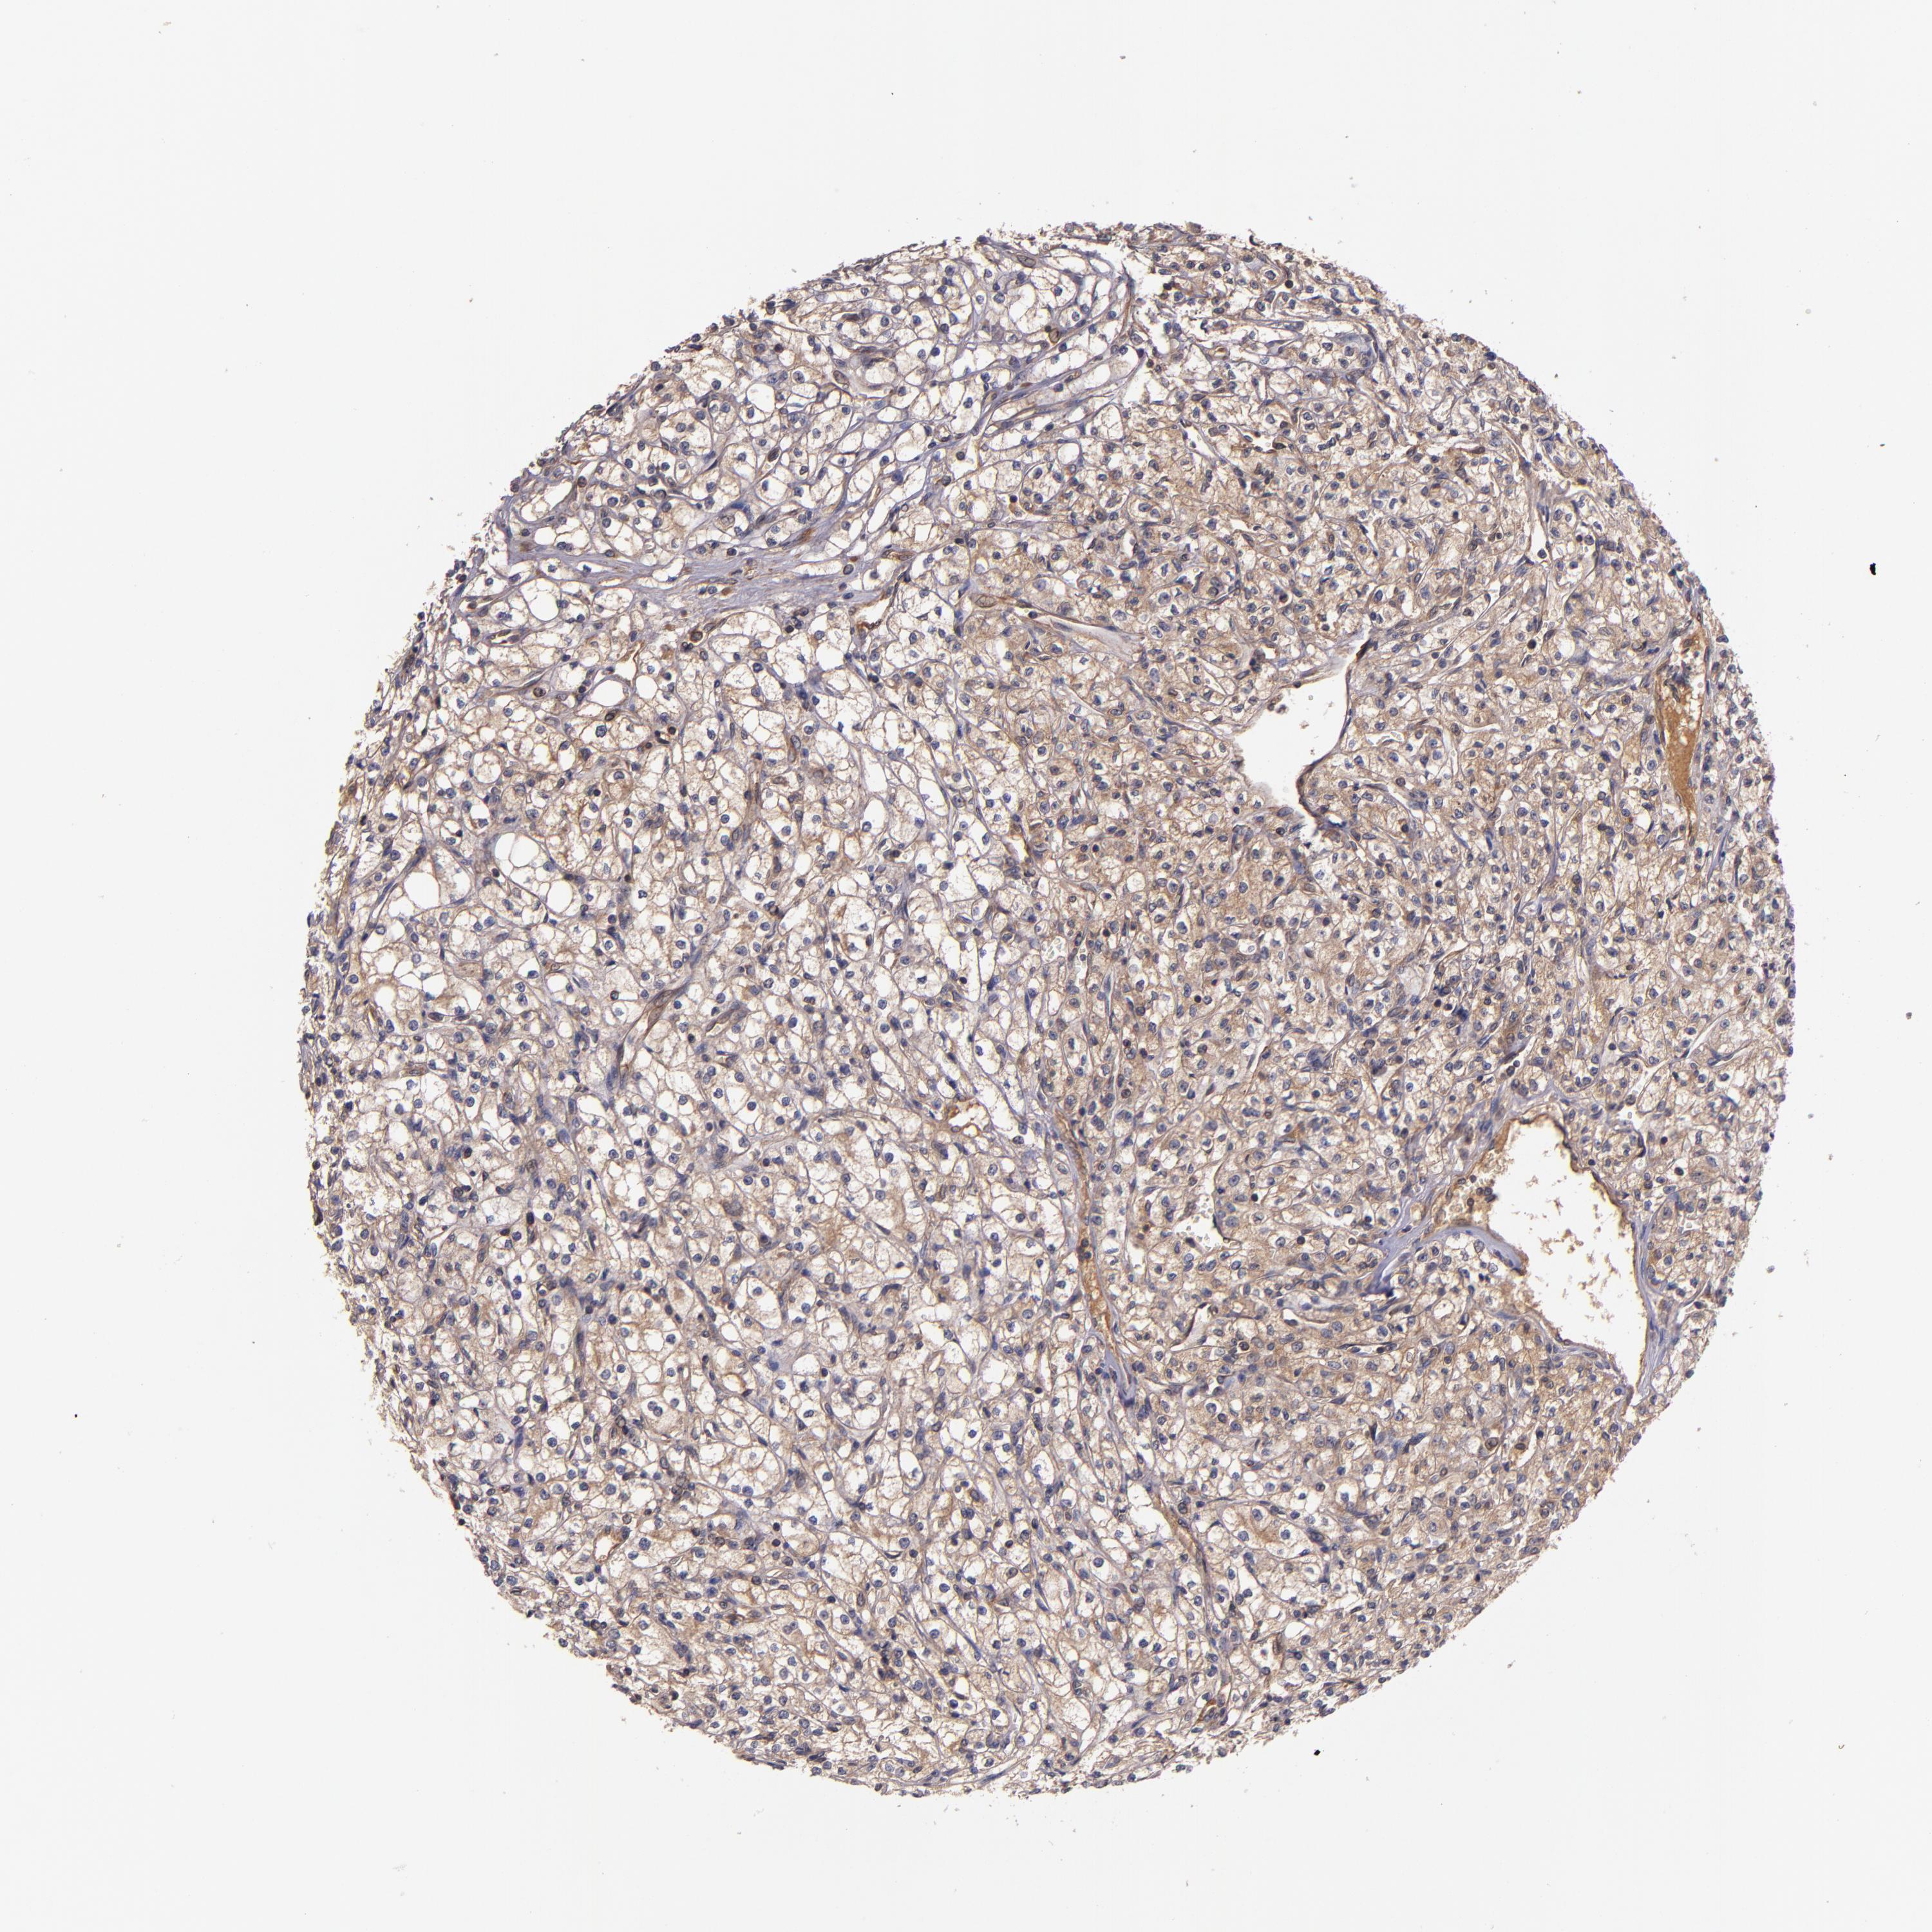

KIDNEY RENAL CLEAR CELL CARCINOMA (VALIDATION) - Interactive survival scatter ploti

The Survival Scatter plot shows the clinical status (i.e. dead or alive) for all individuals in the patient cohort, based on the same data that underlies the corresponding Kaplan-Meier plots. Patients that are alive at last time for follow-up are shown in blue and patients who have died during the study are shown in red.

The x-axis shows the expression levels (FPKM) of the investigated gene in the tumor tissue at the time of diagnosis. The y-axis shows the follow-up time after diagnosis (years). Both axes are complimented with kernel density curves demonstrating the data density over the axes. The top density plot shows the expression levels (FPKM) distribution among dead (red) and alive patients (blue). The right density plot shows the data density of the survived years of dead patients with high and low expression levels respectively, stratified using the cutoff indicated by the vertical dashed line through the Survival Scatter plot. This cutoff is automatically defined based on the FPKM cutoff that minimizes the p-score. The cutoff can be changed by dragging the vertical line or by entering a cutoff value in the square labeled "Current cut-off".

Under the Survival Scatter plot the p-score landscape (black curve; left axis) is shown together with dead median separation (red curve; right axis). Dead median separation is the difference in median mRNA expression between patients who have died with high and low expression, respectively. It is calculated as follows: median FPKM expression of dead patients with high expression - median FPKM expression of dead patients with low expression. This is intended to aid the user in visually exploring custom cutoffs and the associated p-scores and dead median separation.

Individual patient data is displayed and can be filtered by clicking on one or more of the category buttons on the top of the page. Categories describing expression level and patient information include: high, low, alive, dead, female, male and tumor stages. The scale of the x-axis can be toggled between linear and log-scale by clicking on the "x log" button. Mouse-over function shows TCGA ID, patient information and mRNA expression (FPKM) for each patient.

& Survival analysisi

Kaplan-Meier plots summarize results from analysis of correlation between mRNA expression level and patient survival. Patients were divided based on level of expression into one of the two groups "low" (under cut off) or "high" (over cut off). X-axis shows time for survival (years) and y-axis shows the probability of survival, where 1.0 corresponds to 100 percent.

PRAF2 is not prognostic in Kidney Renal Clear Cell Carcinoma (validation)

Best expression cut offi

Based on the FPKM value of each gene, patients were classified into two groups and association between prognosis (survival) and gene expression (FPKM) was examined. The best expression cut-off refers the FPKM value that yields maximal difference with regard to survival between the two groups at the lowest log-rank P-value. Best expression cut-off was selected based on survival analysis .

When clicking on this number, the vertical dashed line indicating cut-off, the interactive survival plot, and the Kaplan-Meier curve will be adjusted to show results based on the best expression cut-off.

: 27.5

P scorei

Log-rank P value for Kaplan-Meier plot showing results from analysis of correlation between mRNA expression level and patient survival.

N/A

TCGA RNA samplesi

RNA-seq data is reported as average FPKM (number Fragments Per Kilobase of exon per Million reads), generated by the The Cancer Genome Atlas (TCGA) .

Normal distribution across the dataset is visualized with box plots, shown as median and 25th and 75th percentiles. Points are displayed as outliers if they are above or below 1.5 times the interquartile range. FPKM values of the individual samples are presented next to the box plot.

Average pTPM 22.6

Number of samples 100